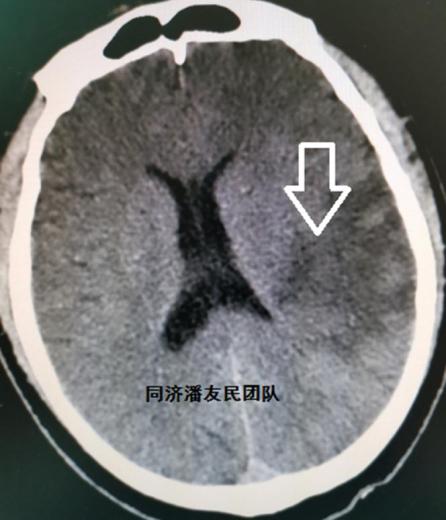

我被家里人送到了医院,从右侧身体不能动和不能说话这个症状,医生很快诊断我是“脑梗”,而且头部CT很快证实了这个诊断(图1)。

鉴于患者脑梗病情稳定,血压控制良好及家属意愿,最终确立保守治疗,待稳定后再手术治疗主动脉夹层。期间复查头部CT,脑梗病灶还合并了少量出血(图6)。